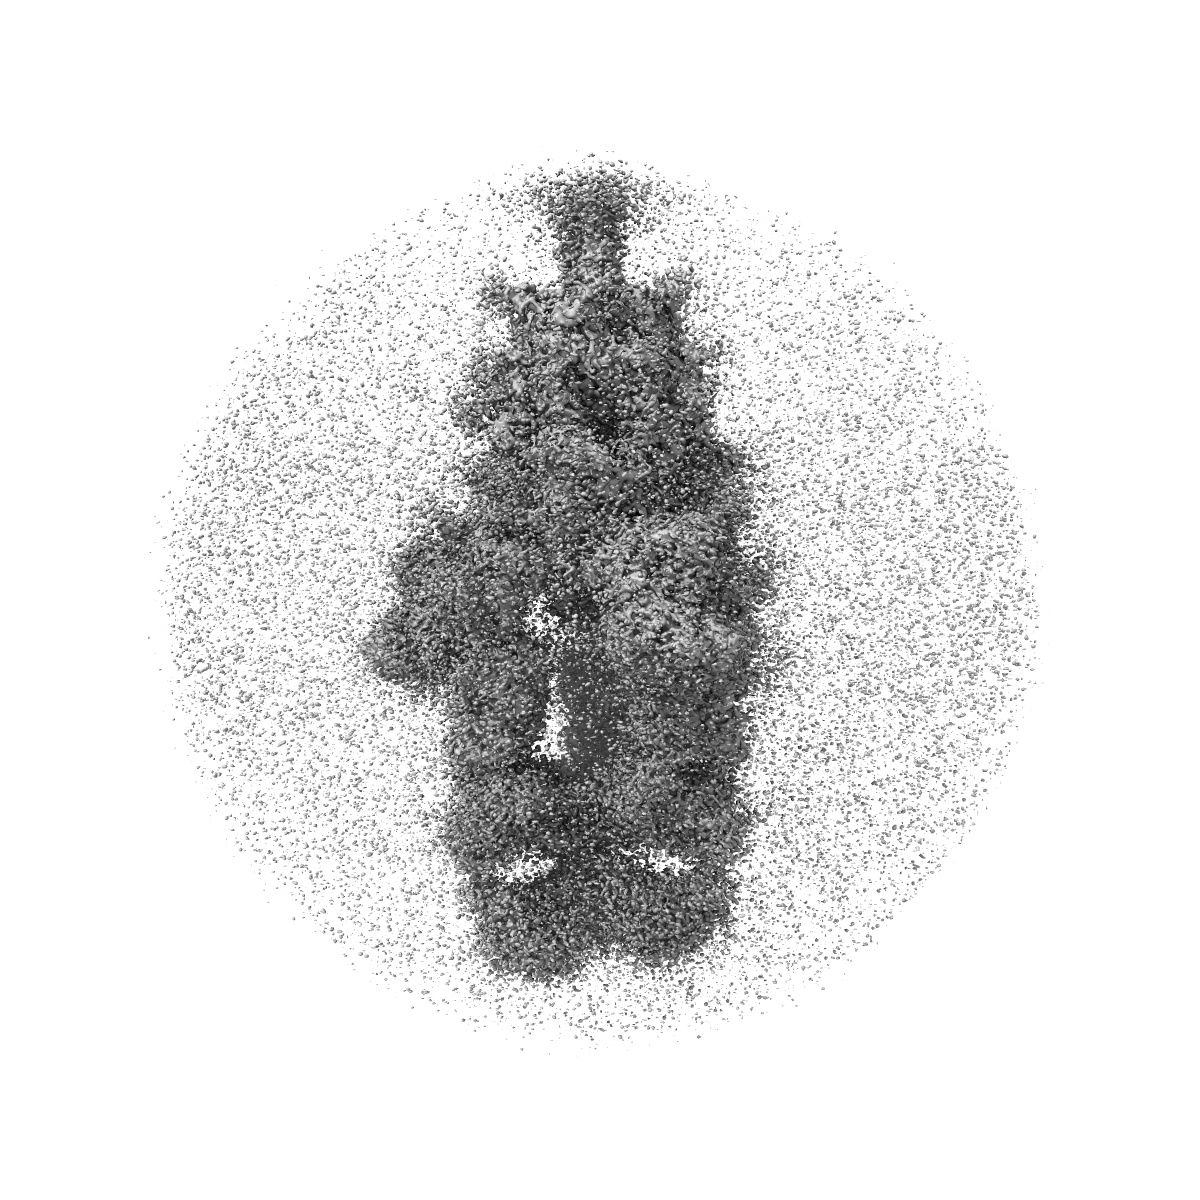

Cryo-EM Structure of SARS-CoV-2 BA.2 Spike protein in complex with BA7535

Single-particle2.44 Å

Sample: Cryo-EM structure of SARS-CoV-2 BA.2 Spike protein in complex with BA7535